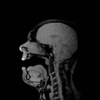

So That’s What it Looks Like When a Baritone Sings in an MRI

Michael Volle hopped into an MRI and sang a Wagner aria so scientists could observe the relationship between loudness and articulation.